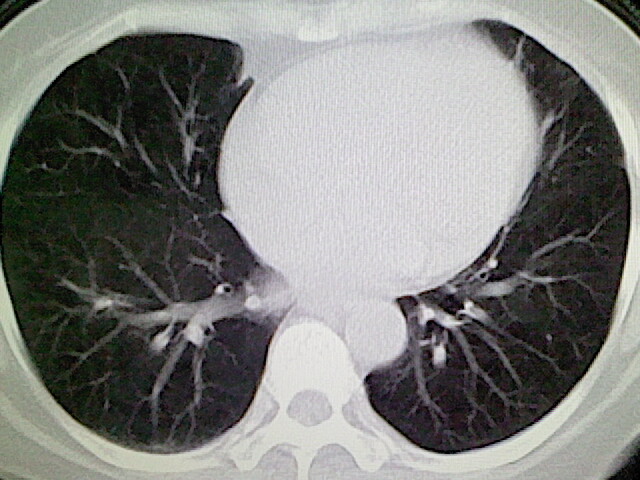

女,52岁,咳嗽,咳痰多日

左下肺陈旧纤维索条!

左肺舌段炎性改变

我见过几例,为炎症后纤维条索

慢性炎症后改变

考虑慢性炎性病灶粘连牵拉改变。

左肺舌叶纤维锁条病变。

左肺上叶下舌段炎症并局部胸膜反应。

左肺舌叶纤维索条影。

左肺舌叶段陈旧性病变

左肺舌段炎性反应。片子的质量太不好了。

左肺舌段炎性

炎性改变

左肺舌叶纤维索条影